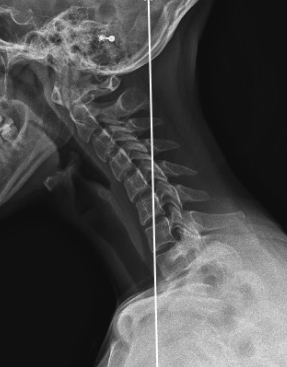

경추(목뼈)는 옆에서 보았을 때 C자 형태로 척추의 정상적인 커브를 나타내고 있어야 하는데 일자 형태의 수직으로 변형된 상태를 말합니다.